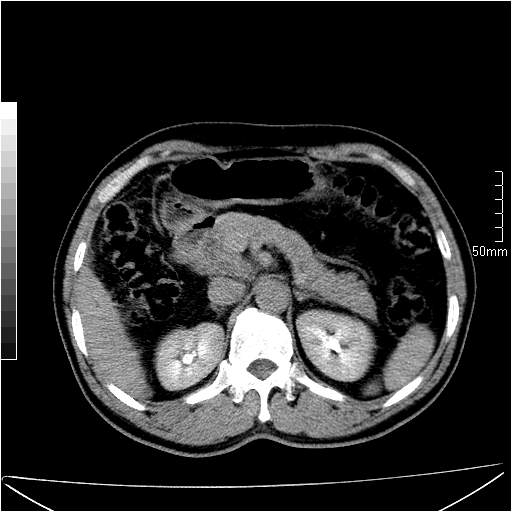

男性,54岁,皮肤黄染,搔痒一周余.b超示肝左叶回声异常.初步诊断1胆总管下段结石2胆囊结石伴慢性胆囊炎请各位战友帮忙看一下肝脏多发低密度如何解释恰当.增强效果不是很好.请大家见谅.

胆总管及肝内胆管扩张,考虑是结石!但,肝内的低密度区增强不明,可能是肝ca,因为肝ca在增强时呈快进快出.另年胆总管扩张原因,可以考虑一下是不是,胆管ca.再次要考虑肝内的低密度是否为海绵状血管瘤所致!

首先,胆总管下端结石梗阻伴肝内胆管扩张可确定。

其次,增强动脉期肝静脉显影,肝实质密度不均。——此为右心功能不全引起肝淤血的表现。

另外,肝八段低密度占位,呈多灶性,考虑肝脓肿或肝癌可能,(图像质量欠佳)建议进一步检查。